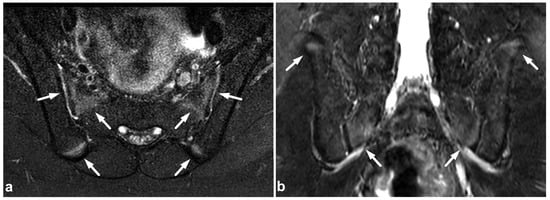

5.3. Nerve Plexus Injuries

Treatment planning in nerve plexus injuries requires dedicated imaging [55,56]. However, in a trauma patient with neurological symptoms in the extremities, the emergency spinal MRI can be extended to immediately confirm or exclude a possible nerve plexus injury (Figure 13). If the dedicated neurography sequences are unavailable, routine fat-suppressed T2-weighted imaging provides good sensitivity in plexus injury detection [56].

Figure 13.

(a) Coronal STIR. (b) Sagittal T2-weighted. The dotted line in the image (a) represents the plane of the sagittal image (b) and vice versa. A 13-year-old male after a moped accident. MRI demonstrates a muscle injury and significant edema at the brachial plexus region (arrows). This emergency imaging was not definitive in assessing the extent of the injury. However, extending the cervical imaging to examine the plexus region tentatively helped to confirm the clinical suspicion of upper extremity paralysis being caused by a brachial plexus injury and not a central nervous system injury.